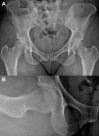

Acetabular labral tears are a known cause of hip pain in the young, active patient. Labral tears can be due to trauma, femoroacetabular impingement, capsular laxity, dysplasia, and degenerative pathology. Paralabral cysts are relatively common in association with labral tears of the hip, with cysts seen on magnetic resonance imaging studies in as many as 50% to 70% of patients with labral tears. In some cases the cysts can become sizeable and cause neurovascular compression. Nonoperative interventions for the management of paralabral cysts in the shoulder and knee have shown high recurrence rates. In the shoulder and knee, arthroscopic debridement of paralabral cysts has shown good results with lower recurrence rates and resolution of neurovascular function. In the hip there is limited literature regarding surgical management of paralabral cysts. We present a surgical technique for arthroscopic decompression of acetabular paralabral cysts combined with labral repair.